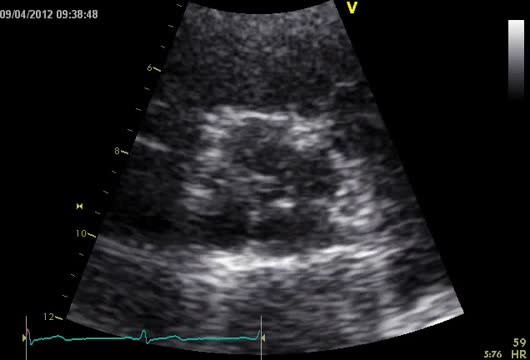

The patient was operated electively. In the operating room, a concentrically hypertrophied left ventricle, dilated ascending aorta and fibrosed quadricuspid aortic valve (QAV) with leaflet retraction and a central orifice were observed (Figure 2). The supernumerary leaflet was the smallest and the others were of equal size. The left coronary ostium was tunneled under the commissure, which warranted special care in order to avoid damage during excision of the valve or obstruction by the prosthesis. Cardioplegia was delivered antegradely, directly in the coronary ostia. We also routinely use topical ice slush or cold saline solution as an adjuvant to myocardial protection. A 21-mm St. Jude mechanical prosthesis was implanted and the surgery ended uneventfully. The predischarge echocardiogram showed preserved ejection fraction (50%) and the mechanical aortic valve with normal opening and no paravalvular leak. Transvalvular gradients (maximum/mean) were 22/12 mmHg. No other valve lesions or significant pericardial effusion were found. The patient was discharged on the fifth postoperative day.

She was in sinus rhythm (∼80 bpm) with a diastolic murmur at the apex. The chest X-ray was normal with preserved cardiothoracic index. The preoperative echocardiogram revealed slightly enlarged left chambers (left atrium 46 mm; left ventricular systolic/diastolic diameters 41/59 mm; interventricular septal systolic/diastolic dimensions 11/15 mm, respectively) and preserved contractility (ejection fraction 63%). The aortic valve had four leaflets with preserved opening (no transvalvular gradient was present) but poor coaptation causing severe aortic regurgitation (vena contracta 8 mm) (Figure 1 and Video 1). The ascending aorta measured 36 mm.